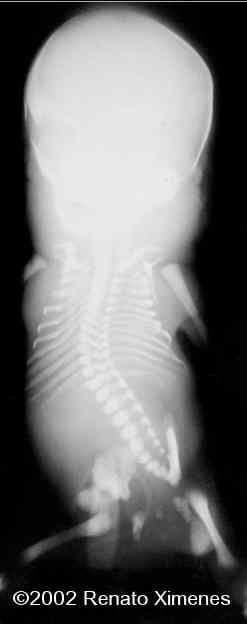

The baby and radiograms

case0072-13

case0072-14